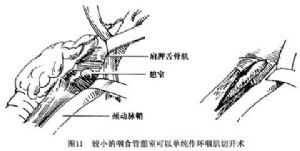

在局麻下沿左側胸鎖乳突肌內側作切口(圖10),暴露咽部及頸段食管,注意保護喉返神經。有Zenker憩室時,對環嚥肌的定位有助。對於較小的憩室可只作環咽肌切開術(圖11)。如憩室中等大小,可將之充分遊離,倒轉後固定縫合在脊柱前筋膜上。如憩室過大或懸吊後過分臃腫,則應將之切除(圖12)。